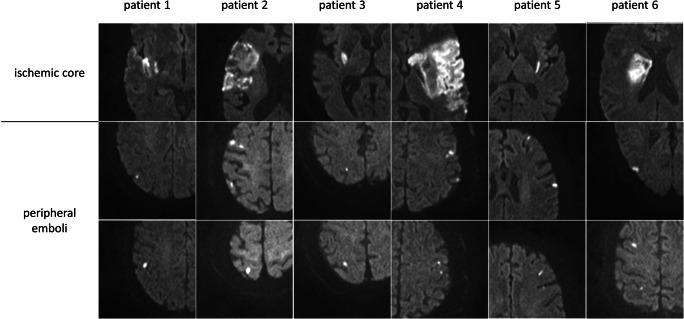

Patients from a prospective study treated at a tertiary care stroke center between 08/2017 and 12/2019 were analyzed. The main inclusion criterion was successful reperfusion after MT (defined as expanded thrombolysis in cerebral infarction (eTICI) scale ≥ 2b50) of large vessel occlusion anterior circulation stroke. All patients received a high-resolution diffusion-weighted imaging (DWI) follow-up 24 h after MT for PE detection. Patients were grouped as "direct MT" (no alteplase) or as MT plus additional intravenous alteplase. The number and volume of ischemic core lesions and PE were then quantified and analyzed.

• Thrombus microfragmentation during endovascular stroke treatment may cause peripheral emboli that are only detectable on diffusion-weighted imaging and may directly compromise treatment effects. • In this prospective study, the application of intravenous alteplase did not influence the occurrence of peripheral emboli detected on high-resolution diffusion-weighted imaging. • A higher degree of recanalization was associated with a reduced number and volume of peripheral emboli and better functional outcome, while contrariwise, peripheral emboli did not modify the effect of recanalization on modified Rankin Scale scores at day 90.